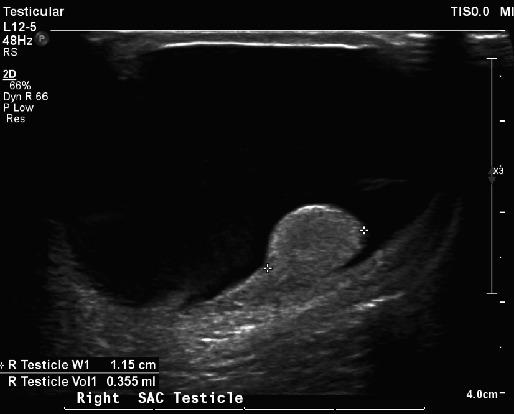

Neonatal testicular torsion (NTT) is a rare but significant condition occurring within the first 30-day postbirth, leading to vascular compromise and potential testicular loss. This paper presents a case of NTT detected incidentally in a neonate with bilateral hydrocele, emphasizing the challenge of early diagnosis and management complexities. The infant underwent surgical intervention involving detorsion and bilateral orchiopexy but eventually required right orchiectomy due to necrosis. The paper highlights the prevalence of NTT in conjunction with hydrocele and stresses the importance of parent education and vigilant follow-up. Various diagnostic methods, primarily ultrasonography, and a range of management strategies are discussed, considering factors such as salvage potential, risk to the contralateral testicle, and surgical intervention's risks and benefits. The paper argues for individualized management, taking into account specific neonate conditions and parental preferences, underlining the essential role of informed and empathetic consultation. The case reinforces the urgent need for increased awareness, early detection, and carefully considered therapeutic approaches to prevent devastating outcomes like infertility and the necessity for lifelong hormone supplementation.

新生儿睾丸扭转(NTT)是一种罕见但严重的病症,发生在出生后的前30天内,会导致血管受损并可能导致睾丸丧失。本文介绍了一例在患有双侧鞘膜积液的新生儿中偶然发现的NTT病例,强调了早期诊断的挑战和管理的复杂性。该婴儿接受了包括扭转复位和双侧睾丸固定术的手术干预,但最终由于坏死而需要进行右侧睾丸切除术。本文强调了NTT合并鞘膜积液的患病率,并强调了家长教育和密切随访的重要性。讨论了各种诊断方法,主要是超声检查,以及一系列管理策略,同时考虑了挽救潜力、对侧睾丸的风险以及手术干预的风险和益处等因素。本文主张个体化管理,考虑到特定新生儿的情况和家长的偏好,强调了知情且富有同情心的咨询的重要作用。该病例强化了提高认识、早期发现以及谨慎考虑治疗方法以预防诸如不育等灾难性后果的迫切需求,以及终身激素补充的必要性。